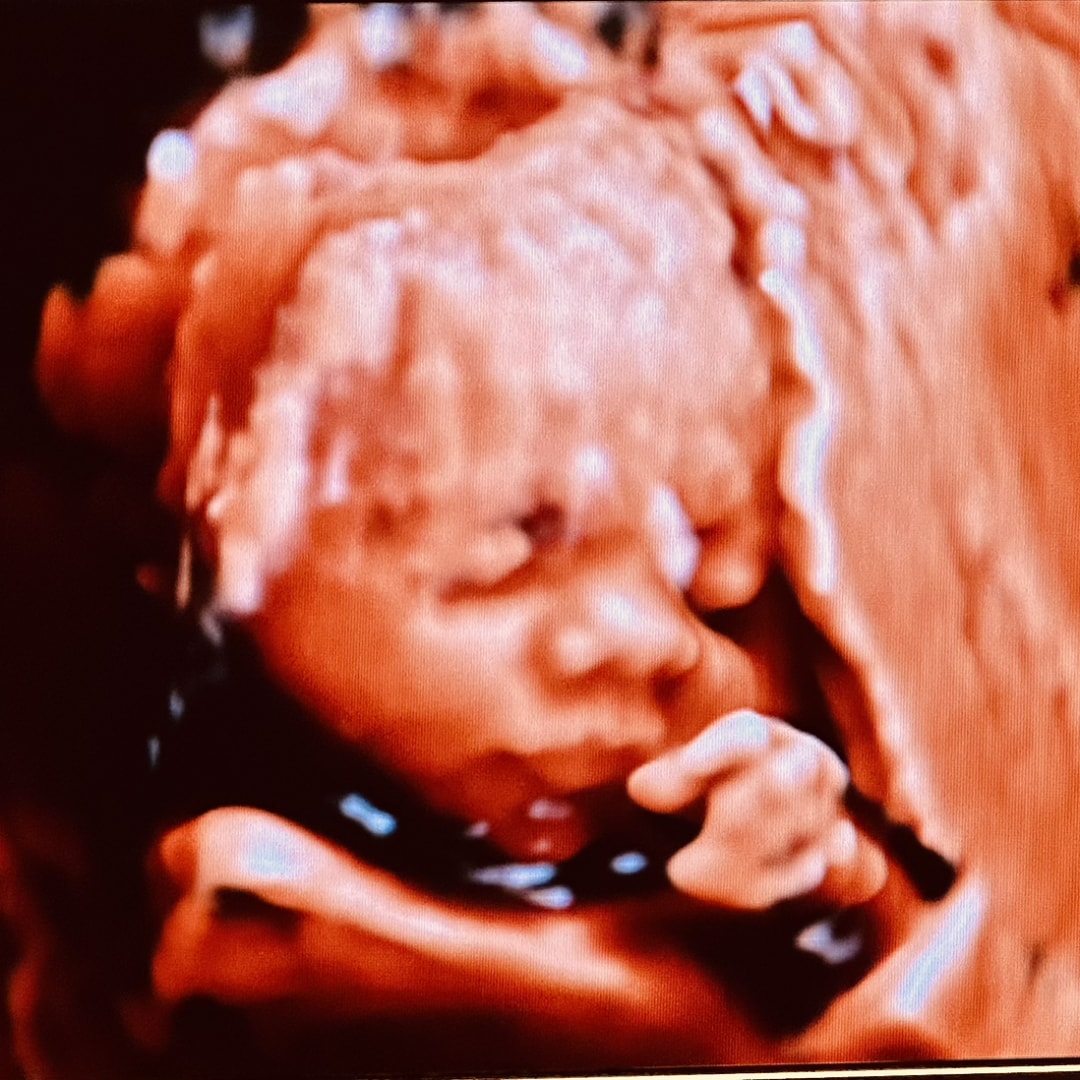

Brandon and I are excited to announce we will be welcoming our sweet baby boy in December! We can’t wait to bring our baby boy into this world, and start our next journey together 🤍 Address: 511 Oak Dr, Randall MN 56475